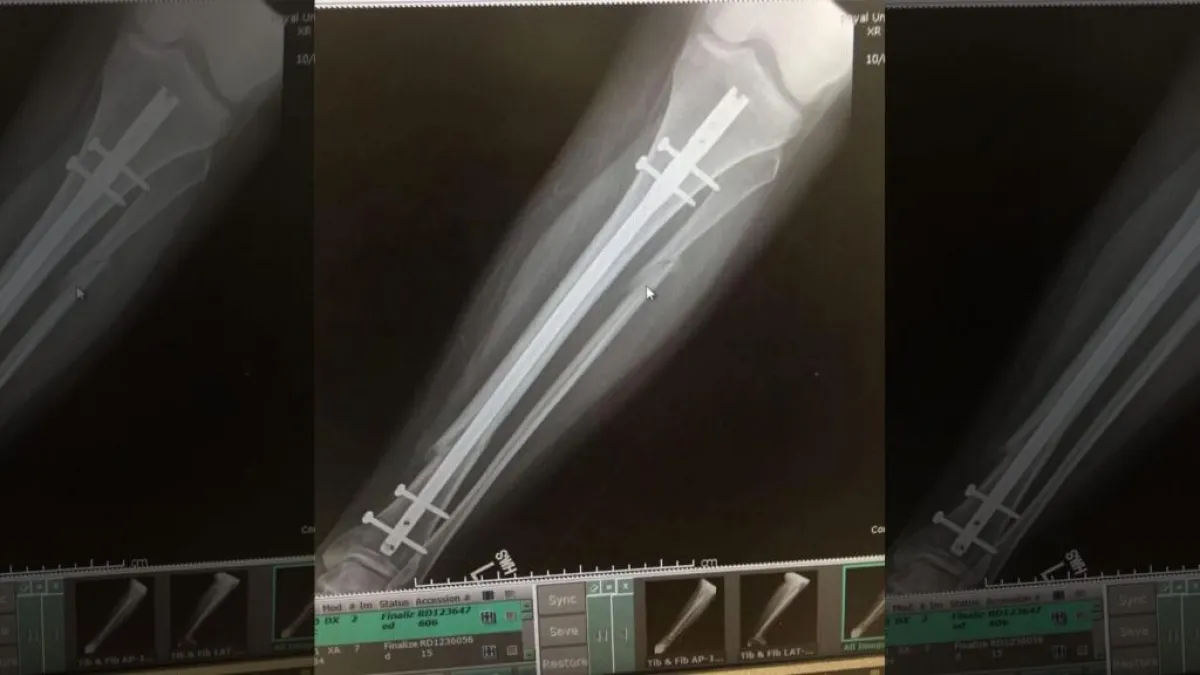

احتاجت «أونين» لعملية جراحية واسعة لإصلاح ساقها، حيث تم وضع قضيب معدني في ساقها، وكانت أيضاً بها مسامير مثبتة في كاحليها وركبتها؛ لمساعدة أطرافها على الشفاء بشكل صحيح.